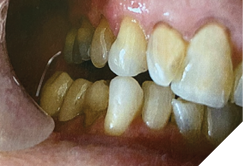

Temporary crowns (Maxitemp HP) compatible with the Gelb appliance were placed. Ten days later, single zirconia crowns (Argen YZ; Shaw Lab, Kingston, Ontario) were permanently cemented using 3M Ketac Cem. Teeth 34 and 33 were built up with composite (Activa, Pulpdent) to restore occlusal contact at the treatment VDO (Fig. 4).

Finally, a cast lower partial denture (Shaw Lab, Kingston, Ontario) was fabricated (Fig. 5ABC). The occlusal design followed anterior/cuspid guidance (Fig. 6). After insertion and minor adjustments, the patient reported comfort and complete resolution of joint symptoms.